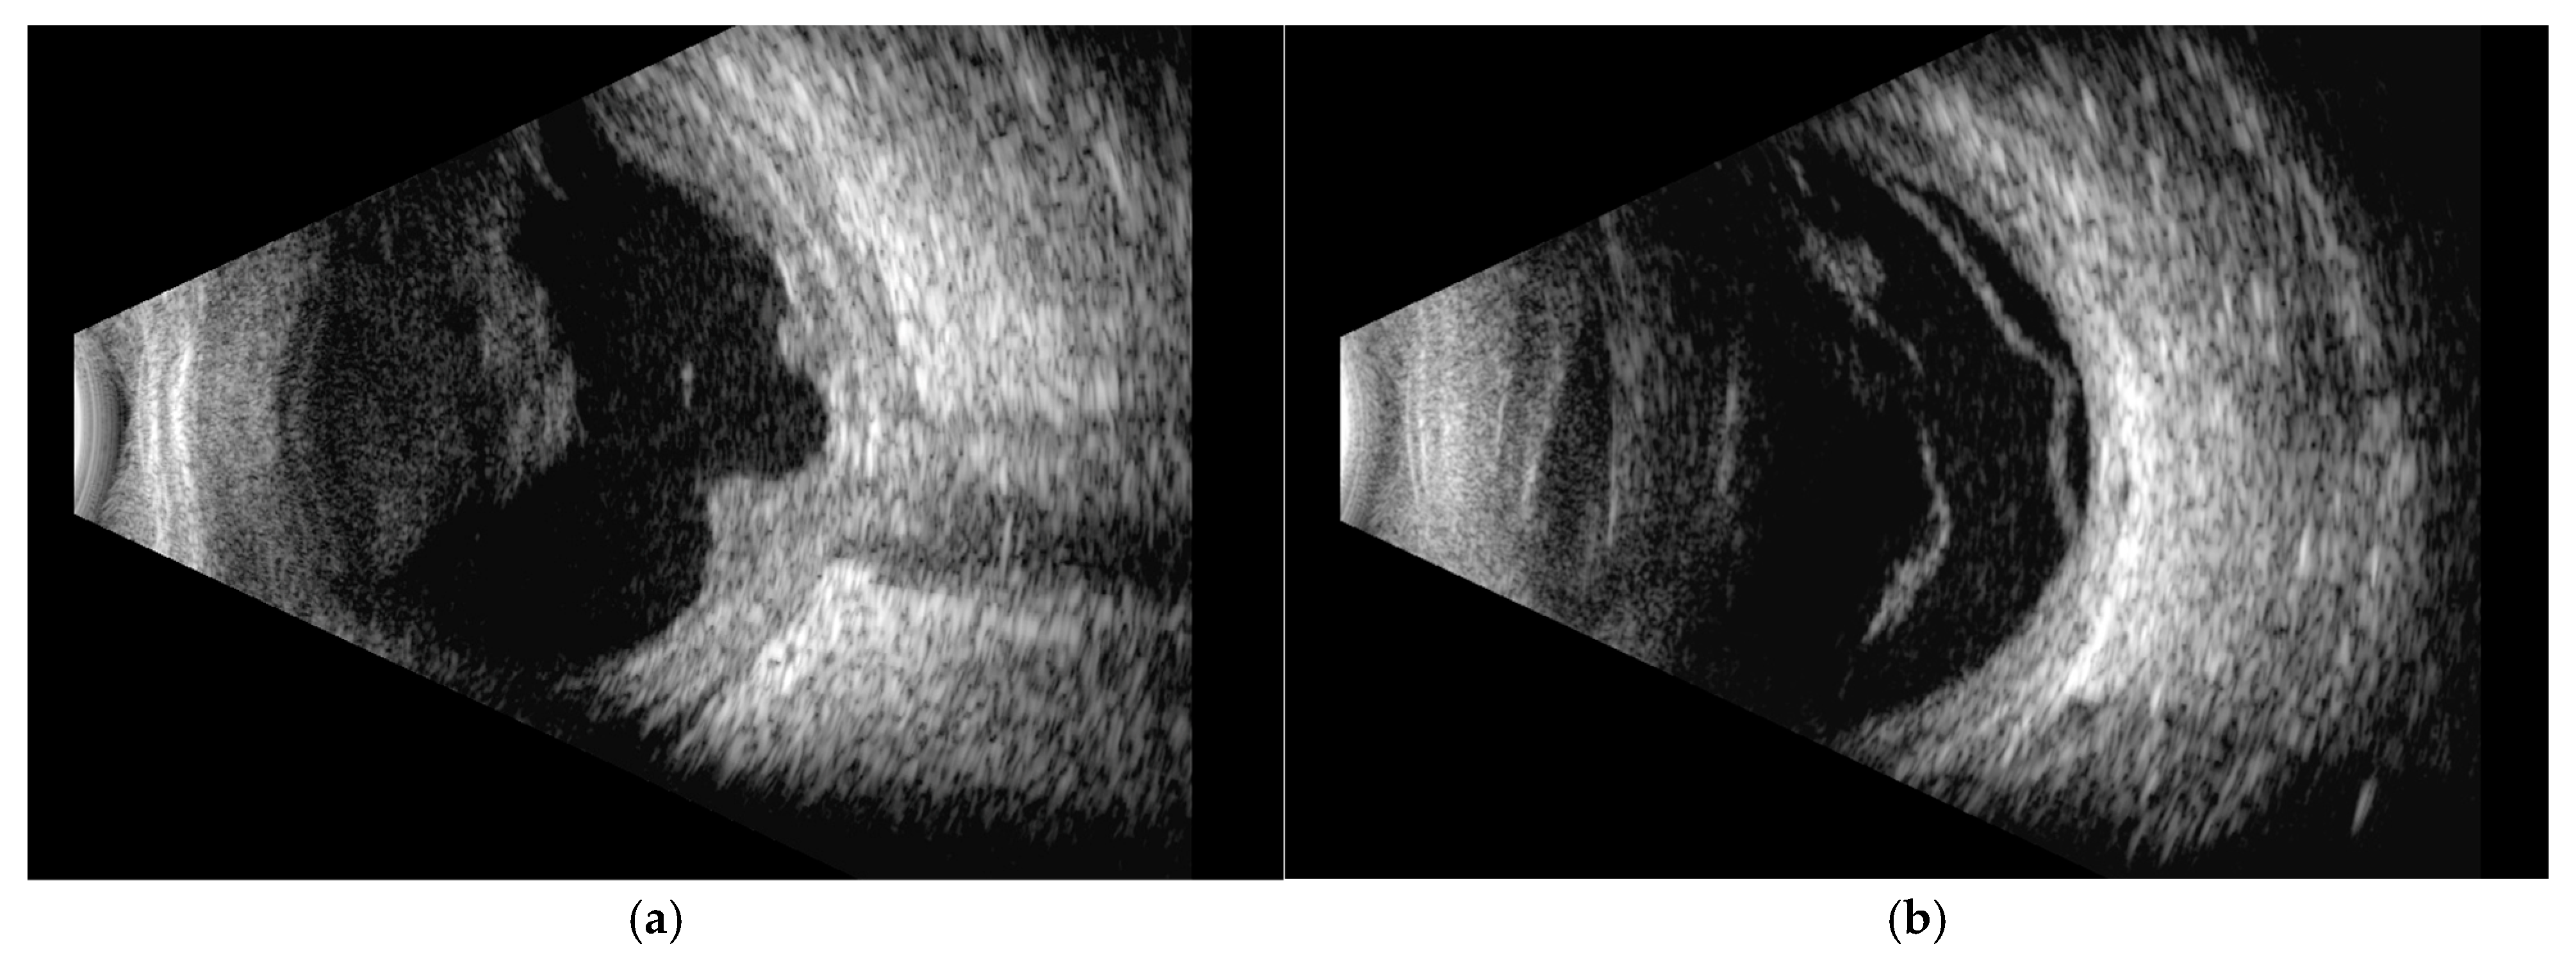

Orbital T2-FLAIR MRI sequences showed mild edema and hyperintensity of the retroorbital and periorbital fat, the lacrimal gland, the posterior sclera, and the optic nerve sheath (Figure 2). B-scan ultrasonography showed fibrotic consolidations and organized vitreous hemorrhage, along with marked choroidal thickening displaying medium–low reflectivity and elevation of the retinal contour, suggestive of infiltrative material (Figure 3). The associated optic disc distortion and perineural sheath edema, together with MRI findings, supported the diagnosis of multifocal leukemic infiltration with adnexal and retrobulbar extension, rather than hemorrhagic changes.

Figure 3. B-scan ultrasonography showing: (a) fibrotic consolidations and organized vitreous hemorrhage; choroidal thickening, alteration of the normal contour of the optic disc head, tram-track sign of the optic nerve sheath and hypoechogenicity of the retroscleral tissue. These findings are suggestive of optic nerve sheath and choroidal infiltration rather than hemorrhagic changes; (b) exudative retinal detachment.